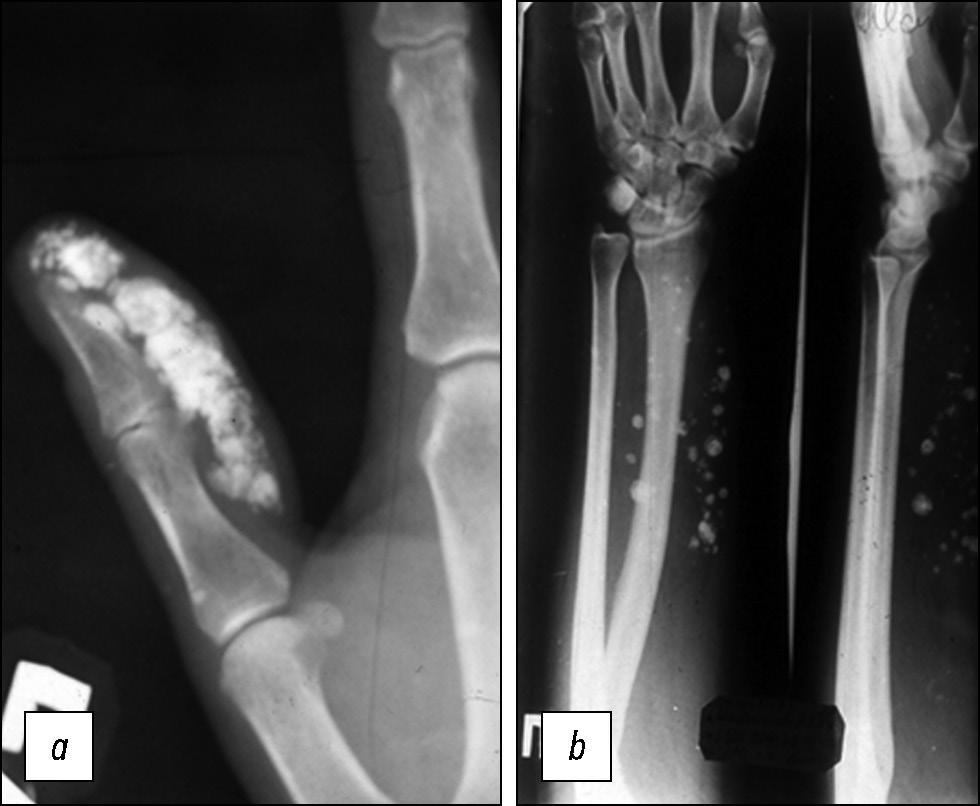

При чтении рентгенограмм обращалось внимание на такие признаки, как наличие дополнительной тени опухоли, тени обызвествления мягких тканей, ограниченная атрофия кости, изменение структуры костной ткани, остеопороз и др. ДОМТ кисти, в особенности при их локализации на пальцах, обычно имеют вид дополнительной тени, иногда более интенсивную плотность (доброкачественные синовиомы, неврилеммомы, фибромы). По форме, характеру и локализации обызвествлений можно отличить доброкачественную опухоль от обызвествлённой гематомы, оссифицирующего миозита, параартикулярных обызвествлений, ограниченного или распространённого кальциноза (рис. 6а). Множественные флеболиты являются патогномоничным признаком гемангиомы (рис. 6b). Наблюдалась локальная атрофия кости от давления медленнорастущей доброкачественной синовиомой, фибромой, неврилеммомой.

Рис. 6. а — параартикулярный кальциноз по ходу сухожильных влагалищ, b — флеболиты при гемангиоме предплечья.

Fig. 6. а — paraarticular calcification along the tendon sheaths, b — flebolity when gemangioma.

Типичная локализация как бы «выбитого пробойником» дефекта кости (рис. 7), а чаще — груботрабекулярная структура ногтевого отростка являются характерными рентгенологическими признаками гломангиомы. При расположении мягкотканного образования между двумя костями происходило смещение.

Рис. 7. Типичная локализация как бы «выбитого пробойником» дефекта кости при гломангиоме.

Fig. 7. Typical localization of a bone defect “punched out” by a glomangioma.